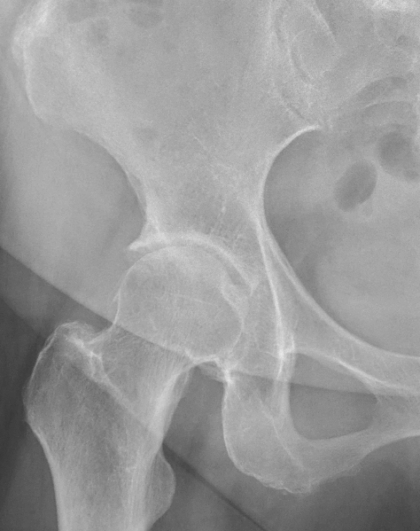

画像検査

X線(レントゲン)検査が基本となり、関節軟骨の厚みの減少(関節の隙間の狭小化)、骨棘(こつきょく:骨のトゲ)、骨嚢胞(こつのうほう:骨の中にできる空洞)の形成などを確認します 。必要に応じて、MRI検査で軟骨や周囲の軟部組織の状態をより詳細に評価します 。血液検査は、他の炎症性疾患との鑑別のために行われることがあります。

病期分類

X線所見に基づき、病気の進行度を前期、初期、進行期、末期のように分類し、それぞれの段階に応じた治療方針を決定します。